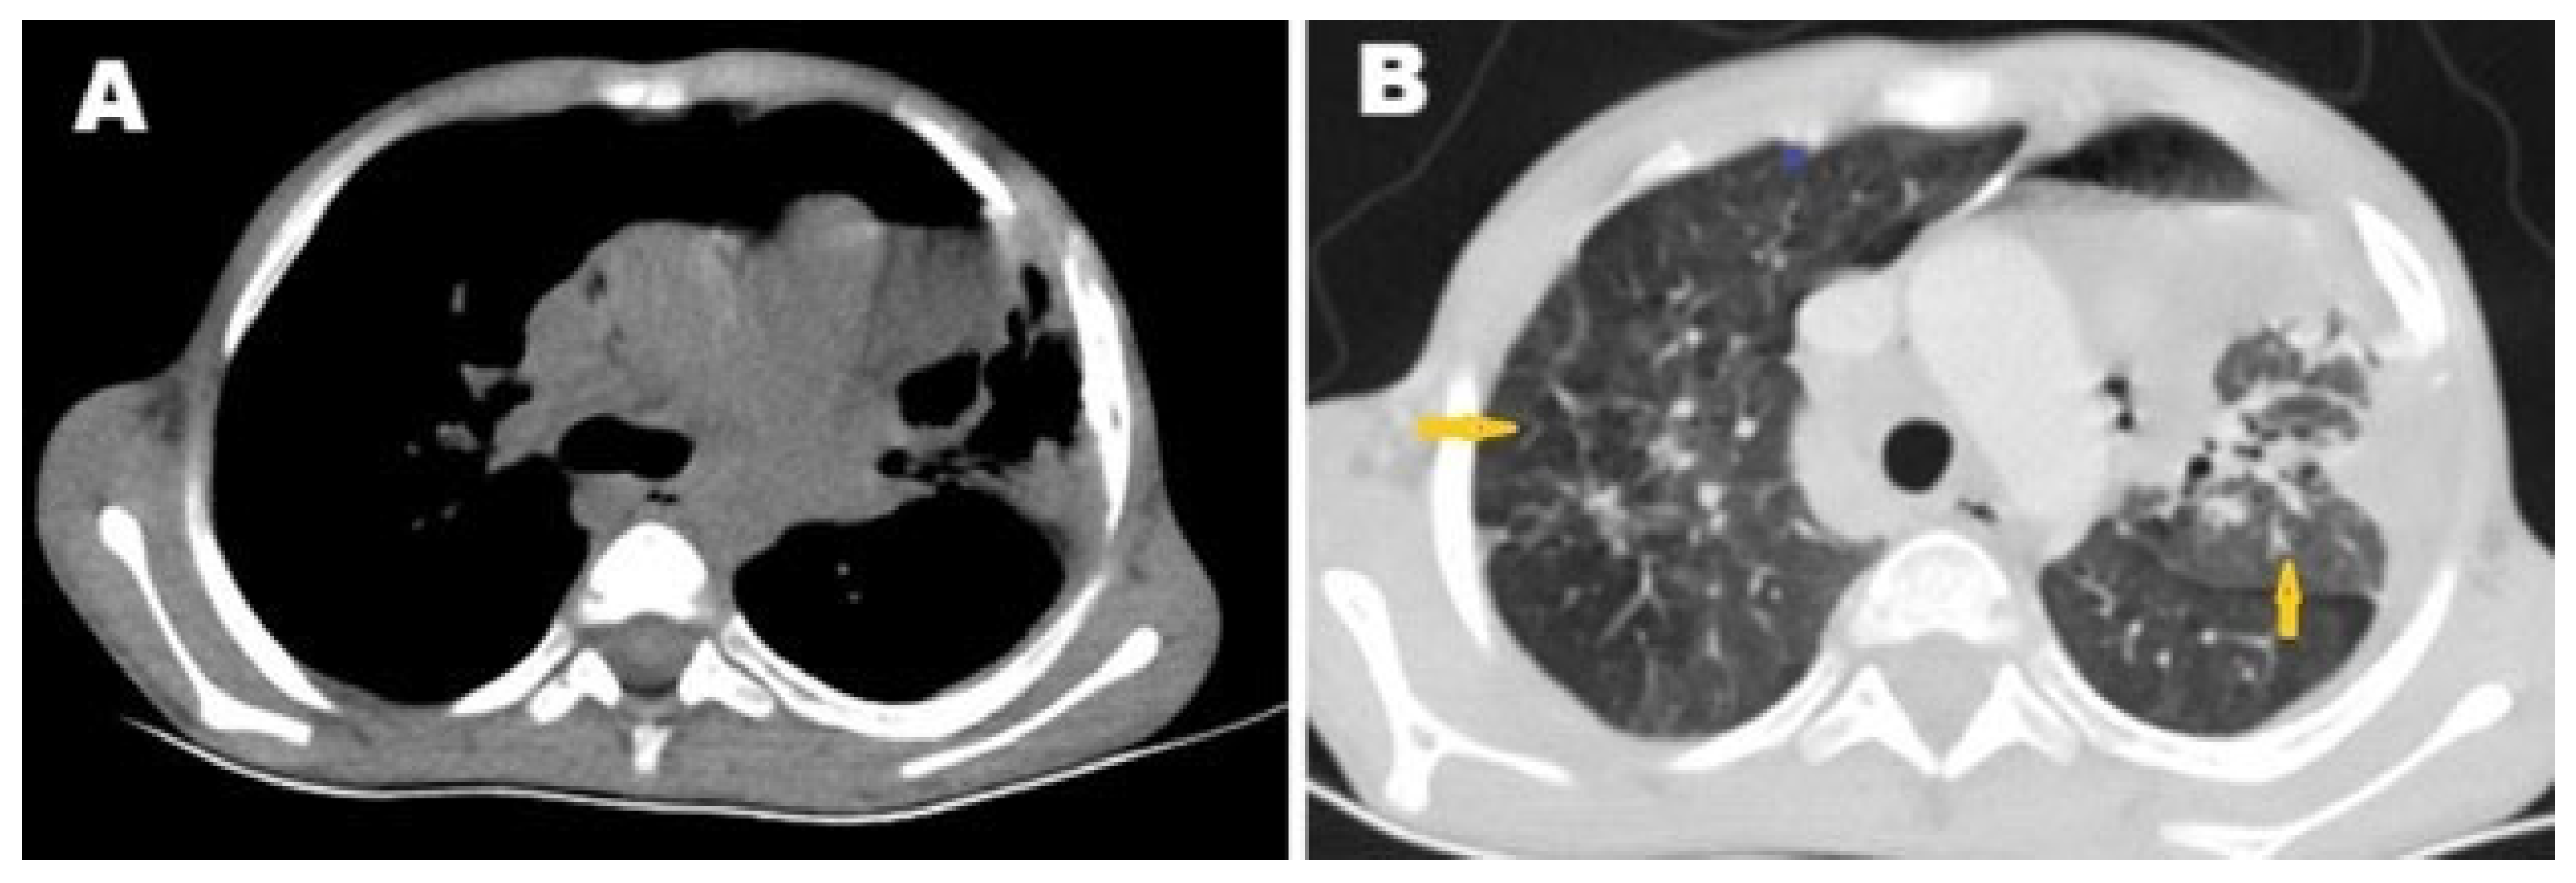

2. Case Presentation